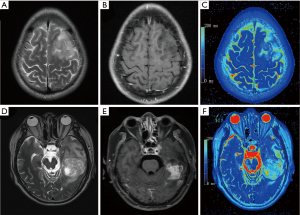

Figure 2 shows examples of T2WI images, T1G images, and the corresponding pseudo-color T2 maps. The median T2 relaxation times of grade II glioma and HGGs were 164.43 (IQR, 147.99, 180.87) ms and 126.75 (IQR, 96.93, 156.57) ms, respectively. The median value of grade II glioma was significantly higher than that of HGGs (P<0.001).